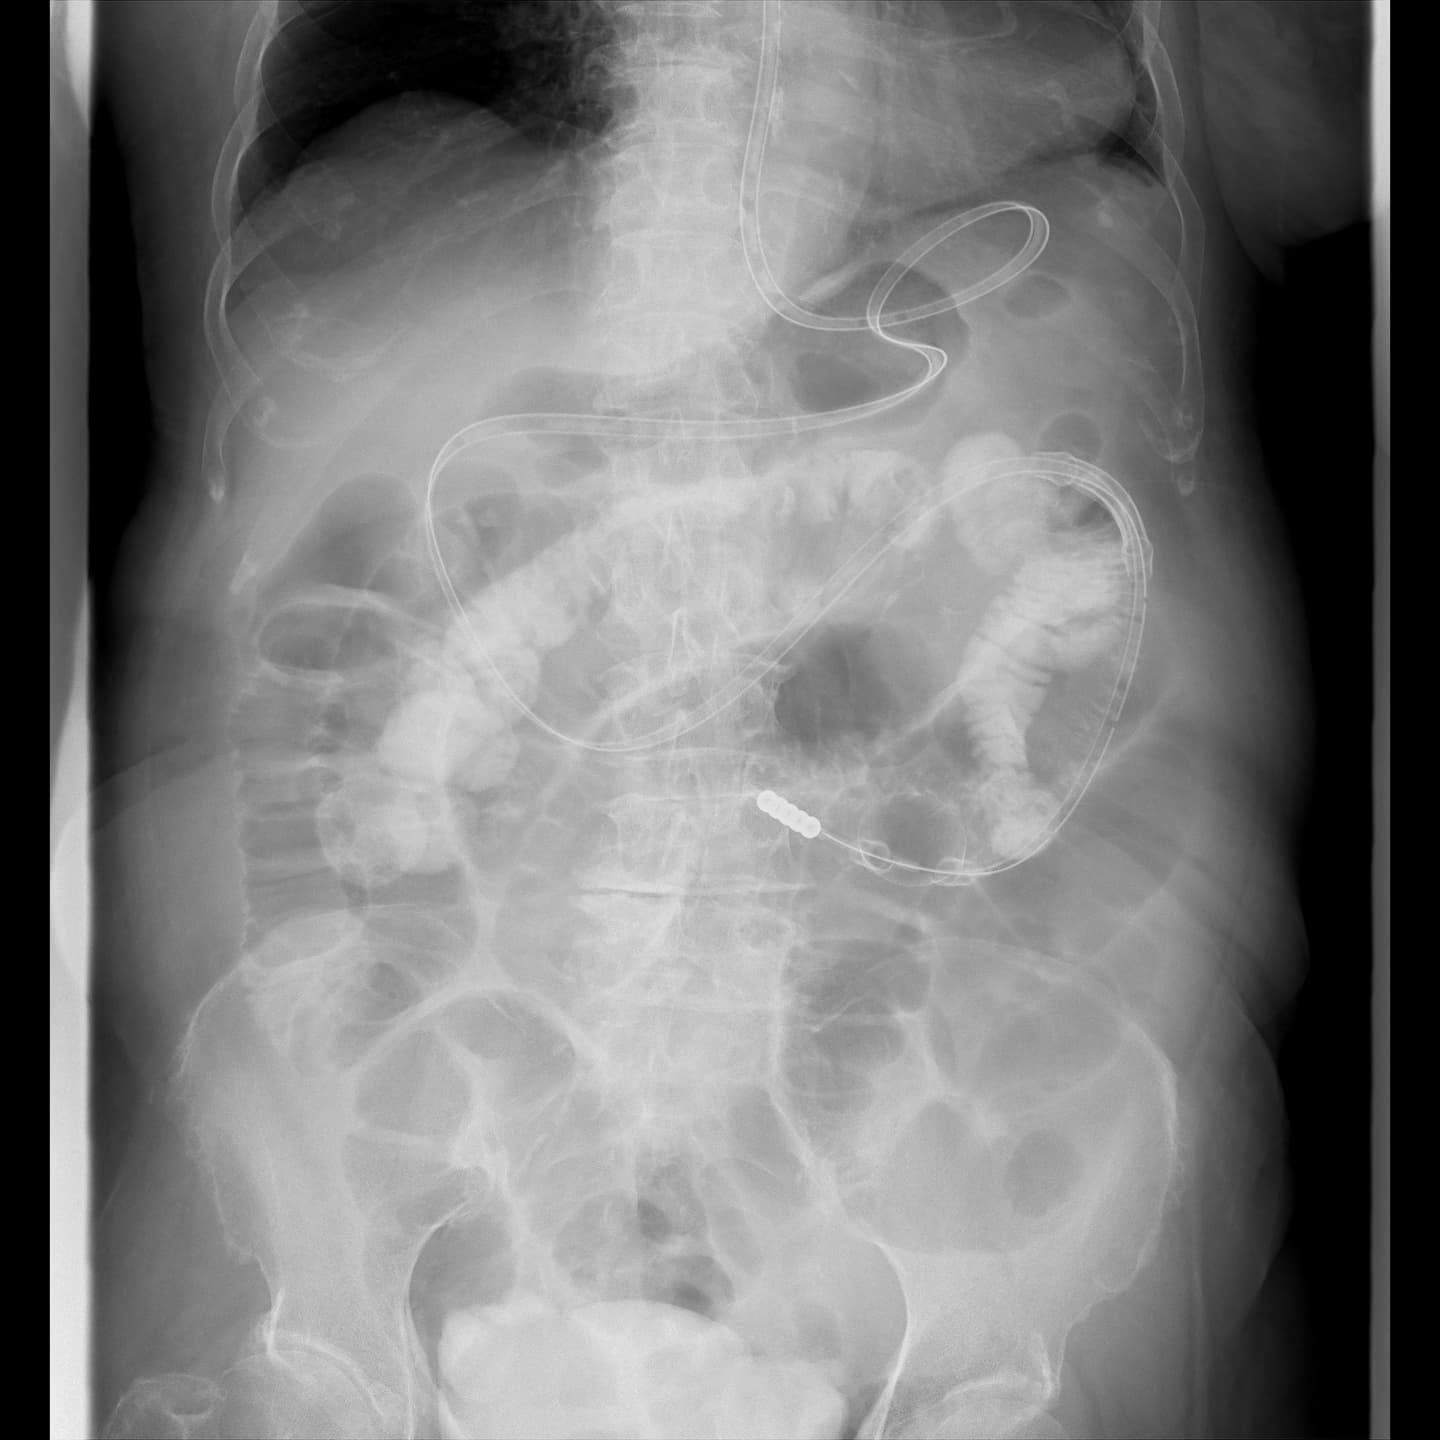

消化器では、バリウムなどの造影剤を使用して、上部消化管(食道・胃・十二指腸など)や下部消化管(大腸など)の造影検査を行っています。

術前精密検査や術後検査として行います。

術後のドレーン管理や、超音波装置を併用したPTCD(経皮経肝胆道ドレナージ)やPTGBD(経皮経肝胆嚢ドレナージ)などの治療も行っています。

消化器の検査も透視検査室5と併用しながら日々検査が行われています。